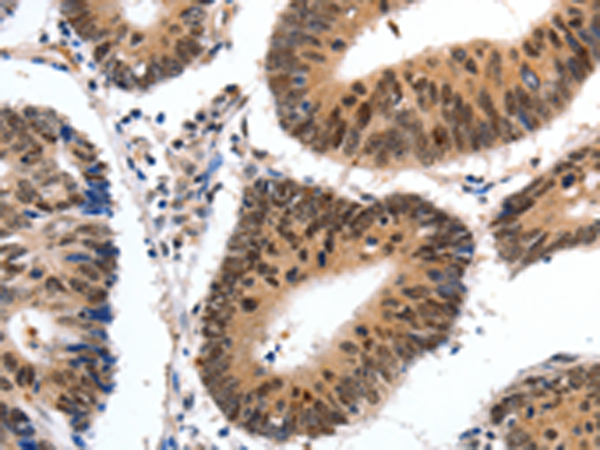

分类: 科研抗体货号: P03961别名: CKLFSF7应用: IHC反应种属: Human